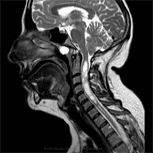

A Doença do Filum é a forma congênita da Síndrome Neuro-Crânio-Vertebral, que consiste em uma tração anormal, causada por um ligamento denominado Filum terminale, que está aparentemente normal. Tal tração afeta todo o sistema nervoso central, ante um crescimento desajustado entre a coluna vertebral e a medula espinhal.

Segundo as nossas pesquisas, esta força de tração, que o ligamento Filum terminale transmite a todo o sistema nervoso, pode se manifestar por meio de várias patologias ou doenças conhecidas, tais como: Síndrome de Arnold Chiari I, Siringomielia e Escoliose idiopáticas, Platibasia, Invaginação Basilar, Retroflexão do Odontóide e Angulação do tronco cerebral. Além disso, influi no aparecimento de outras, como: protrusões e hérnias de disco vertebrais, luxações vertebrais, estenose do canal vertebral, doença cerebrovascular, síndrome da faceta articular vertebral, síndrome de Baastrup, Fibromialgia, síndrome de fadiga crônica e enurese noturna.

A Doença do Filum se manifesta, em cada caso, com um quadro clínico distinto, com sintomas correspondentes a lesões ou malformações provocadas pelo mecanismo de tração anômala – na medula espinhal, no tronco cerebral, no crânio e na coluna vertebral. Estes sintomas podem ser os seguintes: cefaleia, náuseas, vômitos, dificuldade para engolir, vertigem, perda de memória, dores nas colunas cervical, dorsal e/ou lombar, parestesias, sensibilidade táctil ou térmica alterada, dor e/ou falta de força nos membros, falta de equilíbrio, insônia, dificuldades para caminhar, entre muitos outros. Devido a esta diversidade de sintomas, existe uma grande dificuldade de diagnosticar e compreender esta doença.

O Institut Chiari & Siringomielia & Escoliosis de Barcelona (ICSEB) desenvolveu, com as suas pesquisas, o método médico Filum System® (FS®), que facilita o complexo diagnóstico da Doença do Filum, com as suas múltiplas consequências. Além disso, o FS® possibilita a orientação de um tratamento médico, fisioterapêutico e cirúrgico adequado, mediante técnicas cirúrgicas minimamente invasivas, o que permite a recuperação das lesões reversíveis do sistema nervoso e, em alguns casos, as mudanças anatômicas favoráveis desejadas, tais como: o desaparecimento da cavidade siringomiélica, a subida das amígdalas cerebelosas, a retificação parcial ou total da coluna vertebral ou a diminuição das discopatias vertebrais.